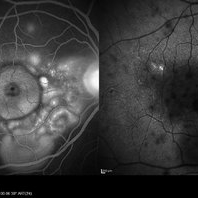

VOGT KOYANAGI HARADA

Oct 7 2015 by Avris Romario Diparaja Siahaan

Fundus photograph of a 42-year-old woman with a Harada Syndrome in both eyes.

Photographer: Avris Romario Diparaja Siahaan, Klinik Mata Nusantara

Imaging device: Topcon TRC 50DX IA

Condition/keywords: color fundus photograph, Vogt-Koyanagi-Harada